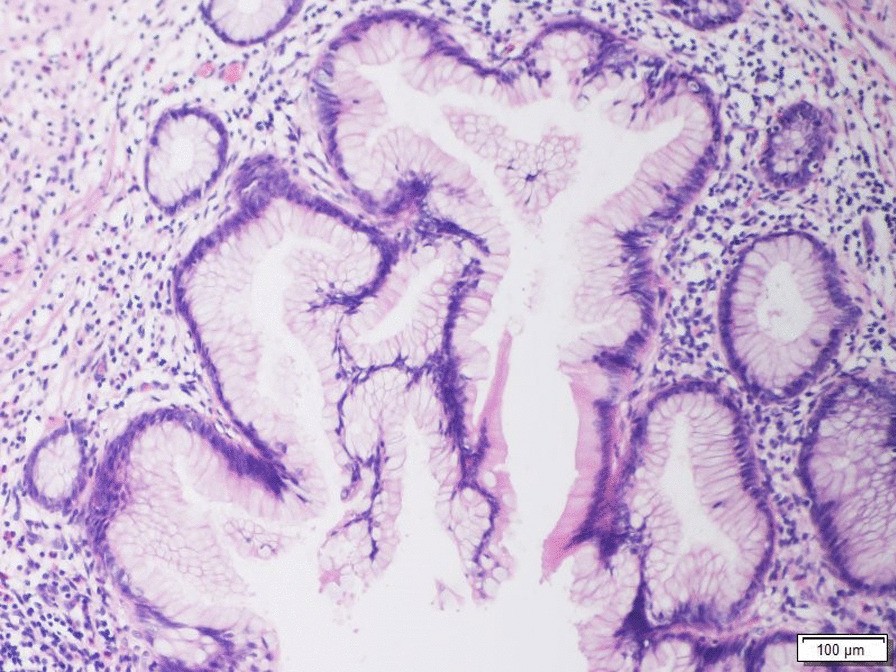

Histological section of a low-grade appendiceal mucinous neoplasm